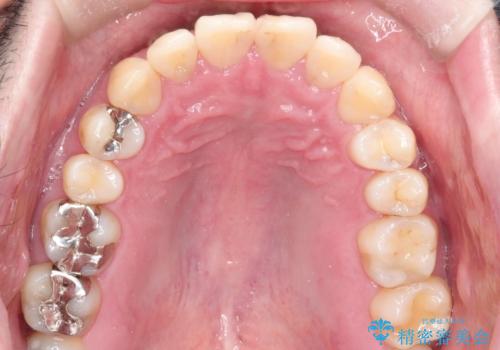

全体的ながたつきをインビザラインで改善

- 全体的ながたつきを主訴に来院されました。

歯と歯の間をわずかに削って、スペースをつくり並べる計画としました。

しっかりと、マウスピースの装着時間を守っていただいたので、スムーズに治療をおえることができました。